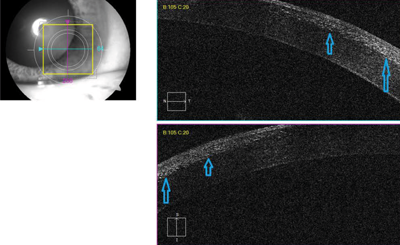

Anterior segment OCT showed diffuse hyper-reflective dots in the flap-stromal interface (Figure 3). A clinical diagnosis of diffuse lamellar keratitis was made.

Figure 3: Anterior segment OCT showed diffuse hyper-reflective dots in the flap-stromal interface.